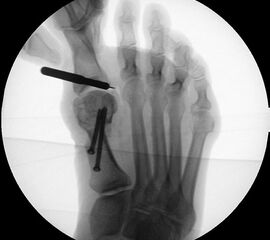

Abbildung 1

• Korrekturpotential größer als beim offenen Chevron, da die Gelenkkapsel als stabilisierendes Element erhalten bleibt und über eine trikortikale Osteosynthese mit zwei kanülierten Schrauben eine Verschiebung bis ca. 80% des Metatarsaledurchmessers möglich ist (Abb. 1).